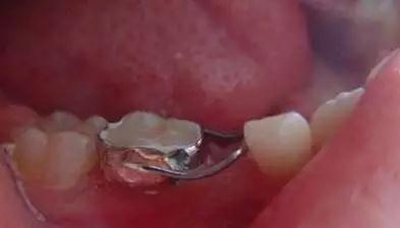

③帶環(huán)絲圈式間隙保持器。

制作:在基牙上做帶環(huán)或全冠,再在其上焊接絲圈,絲圈的頰舌徑比后繼恒牙的頰舌徑稍寬。絲圈與牙尖接觸位置要在其遠(yuǎn)中最突點(diǎn)或稍下方。與第一恒磨牙接觸點(diǎn)應(yīng)在近中外形高點(diǎn)。